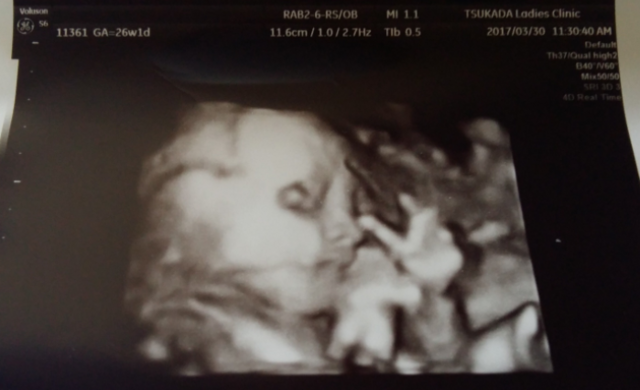

26週1日(26w1d・女の子)|chi1992 さん(25歳)

エコー写真撮影時のエピソード:

初めてお顔を見せてくれてどっちに似てるのかなって話しながらお腹に声をかけました。

こんなに狭い所で苦しくないかな~とか それまでは気にしなかった事もお顔を見た瞬間 全ての行動が気になってしまって苦しくないかなとか食べ物とかちょっとした振動でも気になるようになりました。

産院からは低置胎盤かもと言われていましたが無事6/3に2870gの元気な女の子が私達の元に来てくれました。 エコー写真でしか今まで会えなかったのが大きな産声聞けて本当に本当に幸せです。